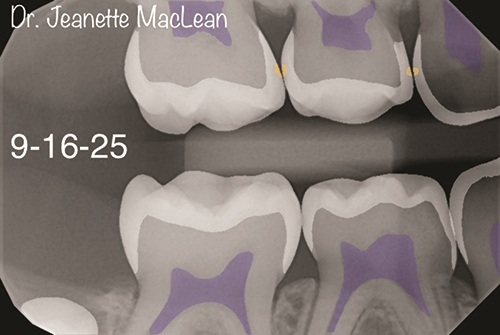

Figs. 3a and 3b: Five-month follow-up BWs (DEXIS Titanium imaging).

Figs. 4a and 4b: Overjet confirms the incipient lesions are stable after treatment with silver diamine fluoride (Advantage Arrest, Elevate Oral Care). The lesions between the mandibular right primary molars are no longer detectable.